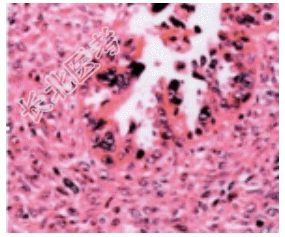

- [材料题] 患者女性,56岁,主诉下腹不适,妇科检查发现左侧附件肿物如儿头大小,手术切除卵巢肿瘤。肿瘤镜下病变如图示,间质细胞成份有异型,病理诊断为卵巢癌肉瘤。

- 简答题1、该疾病的大体改变为?

- 简答题2、该疾病的镜下改变表现为?

- 简答题3、该疾病需与哪些疾病进行鉴别诊断?